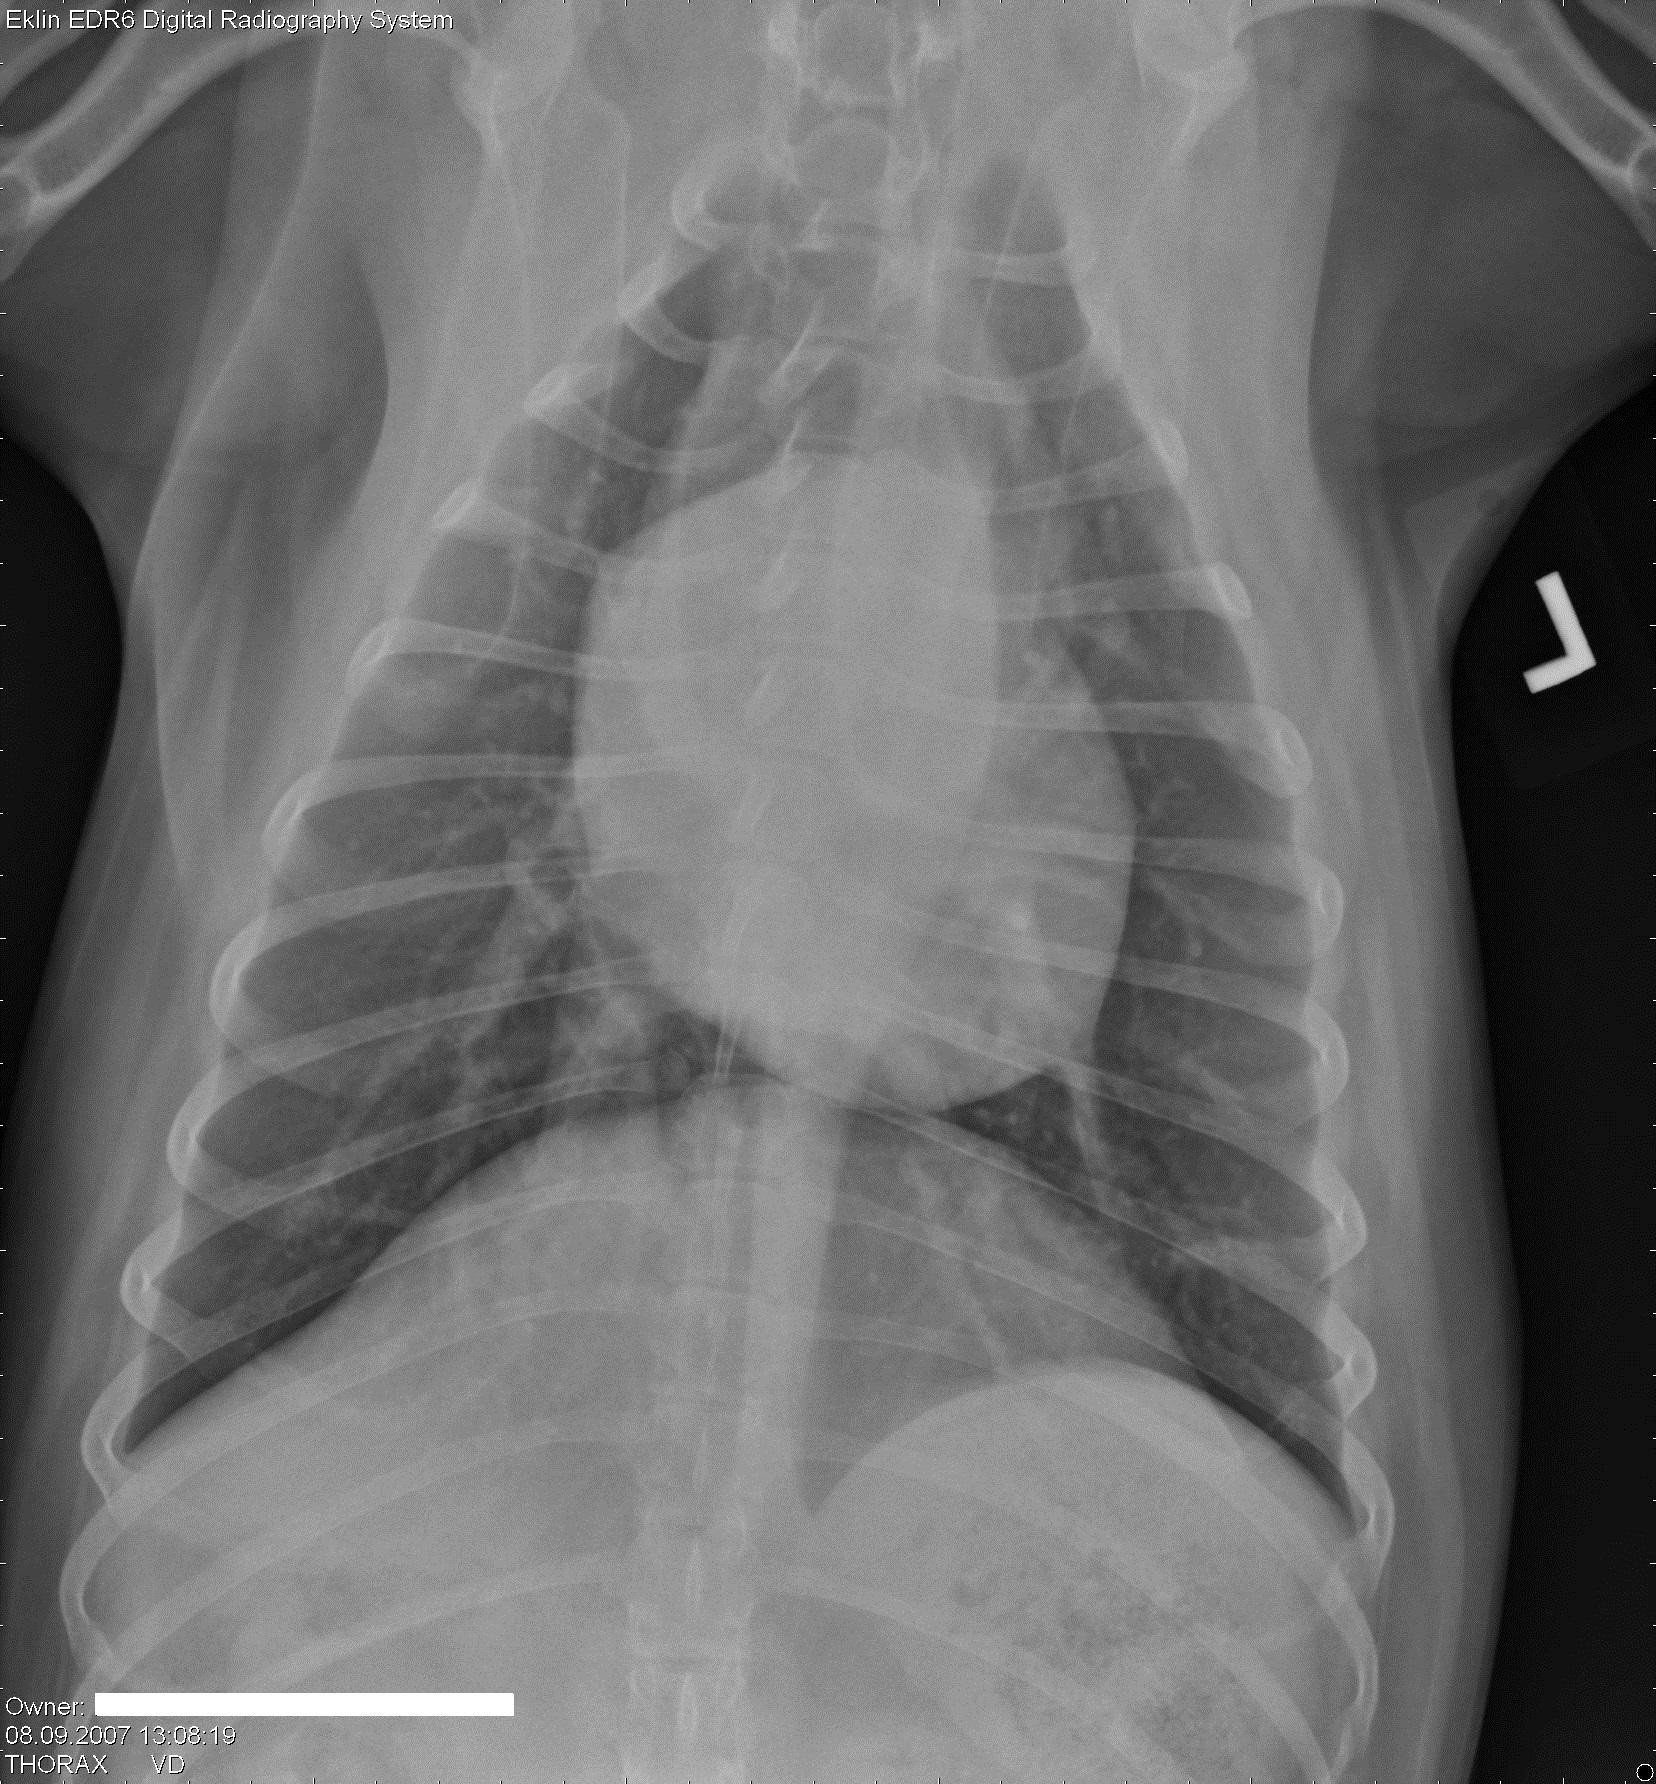

Een 10 jaar oude, mannelijk, gecastreerde hond wordt bij je aangeboden met erge tenesmus.Â

Röntgen foto’s

Hieronder vind je 5 Röntgen foto’s thorax en abdomen. Gebruik de pijltjes om erdoor te schuiven, of klik op de foto om te vergroten.